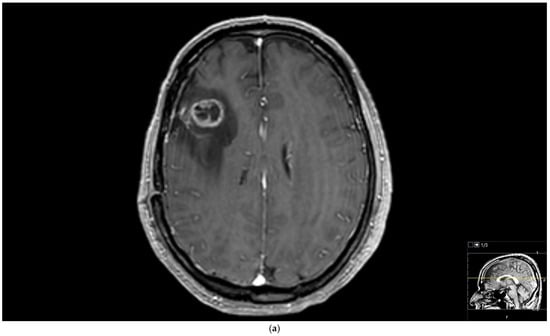

We further performed analyses based on the grade of the glial tumors. Tumoral rCBV values of high-grade glial tumor patients were significantly higher than those with low-grade glial tumors (Figure 3) (p = 0.009). Tumoral and peritumoral rCBV values of patients with high-grade glial tumors were higher than those with brain metastases (Figure 3) (p < 0.001 and p = 0.001). For the lung cancer types, although statistically not significant, there was a trend toward higher values in tumoral rCBV of high-grade glial tumors than small-cell lung cancer patients (p = 0.068). Tumoral and peritumoral rCBV medians of high-grade glial tumor patients were significantly higher than those of non-small-cell lung cancer patients (p < 0.001 and p = 0.003). While the median rCBV in both the tumoral and peritumoral regions of patients with high-grade glial tumors exceeded that of patients with breast cancer, the difference did not attain statistical significance (p = 0.311 and p = 0.053). Tumoral and peritumoral rCBV values were higher in patients with high-grade glial tumors compared to metastasis from miscellaneous organs (p < 0.001 and p = 0.003).

Figure 3.

Brain magnetic resonance imaging (MRI) of a 51-year-old male histopathologically diagnosed with glioblastoma. (a) Increased signal on T2-weighted image with peritumoral edema, (b) peripherally enhanced right frontal subcortical mass on post-contrast axial T1-weighted image, and (c) hyperperfusion with a rCBV of 1.5 in perfusion-weighted imaging (Pink ROI is from tumor and white ROI is from contralateral parenchyma).